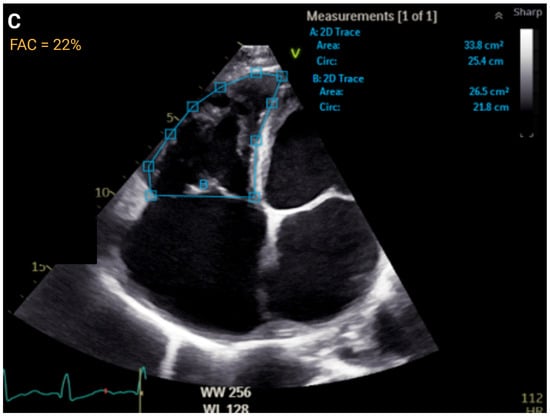

| FAC, % | >35 | ≤35 to >29 | ≤29 to >22 | ≤22 | r = 0.55 to 0.77 | AUC = 0.83 |